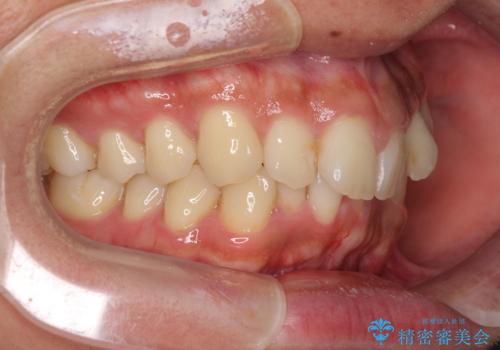

前歯のデコボコをスッキリ改善 インビザライン矯正

- 上下前歯のデコボコを気にして来院された患者様です。

全体的に叢生は軽度であったため、インビザラインにて矯正治療を行うこととしました。

デコボコの改善はもちろん、下顎前歯が隠れてしまうディープバイトも一緒に改善することができ、奥歯への負担を軽減することができました。